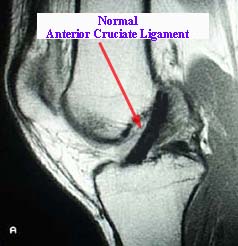

ACL(前十字韌帶)斷裂

因為膝蓋疼痛有好一陣子了,所以麻煩學姐幫我做膝蓋的MRI(磁振造影檢查),懷疑自己膝蓋積水,果不其然,除了積水外,ACL(前十字韌帶)也有部分斷裂現象,這解釋了為什麼我的膝蓋持續疼痛及有時會無力。下面...